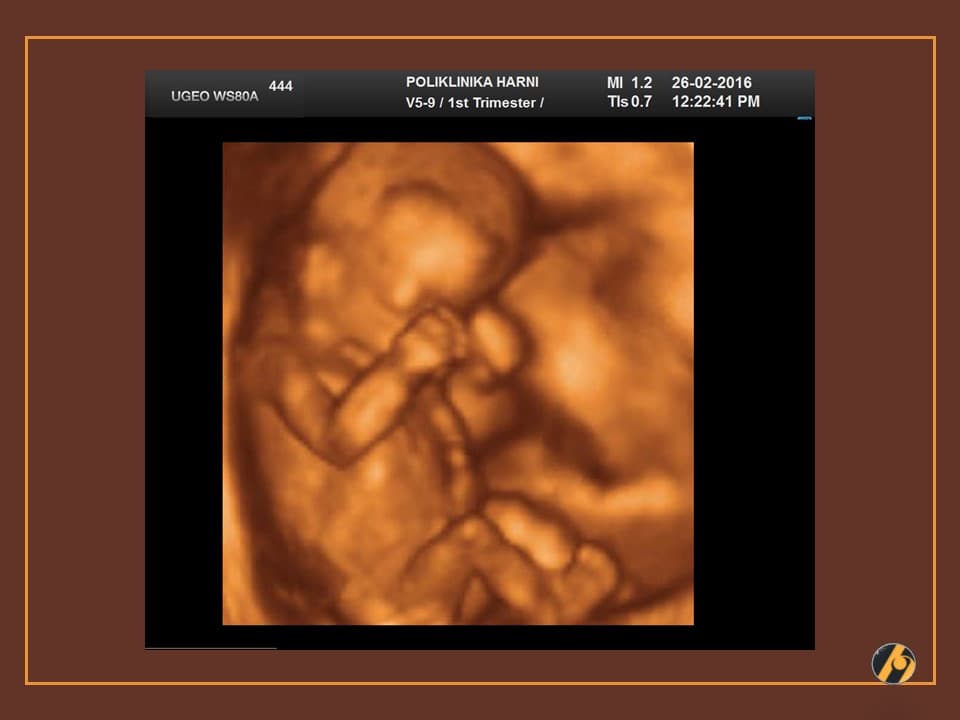

Nastavlja se oblikovanje lica koje je sve više nalik ljudskom licu. Razvitkom noktiju na rukama i nogama završava se razvitak prstića. Beba je veoma pokretna i kod ultrazvučnog pregleda se zapažaju nagli i snažni pokreti tipa trzaja - pokreti su spontanog karaktera, ali bez volje djeteta. U ovo vrijeme je kontrola pokreta djeteta još uvijek podređena živčanim središtima u leđnoj moždini, a moždani centri za koordinaciju pokreta još nisu razvijeni.

U ovome tjednu se crijeva u potpunosti smještaju u trbušnu šupljinu i ukoliko se prije vidjela omphalocoela (prisustvo crijeva u pupčanoj vrpci), sada se ta slika gubi. Formirano je i raspoznatljivo vanjsko spolovilo, koje se standardnim ultrazvučnim tehnikama još neko vrijeme neće moći raspoznati.

Vaša beba dugačka je oko 6.5 cm, a teška 10 - 15 g.